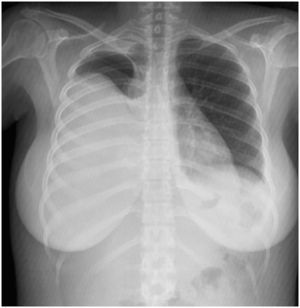

Se documentó derrame pleural derecho masivo (figs. 1–3), se realizó toracocentesis diagnóstica y terapéutica. Se obtuvo líquido pleural clasificado como exudado, con anticuerpos anti-DNA nativo positivos >250U/ml, y cultivos para bacterias, hongos y micobacterias negativos, con citología negativa para células malignas.

Se concluyó derrame pleural masivo secundario a actividad lúpica, y se trató con prednisona en dosis de 1mg/kg de peso y furosemida, con lo que se logró mejoría.